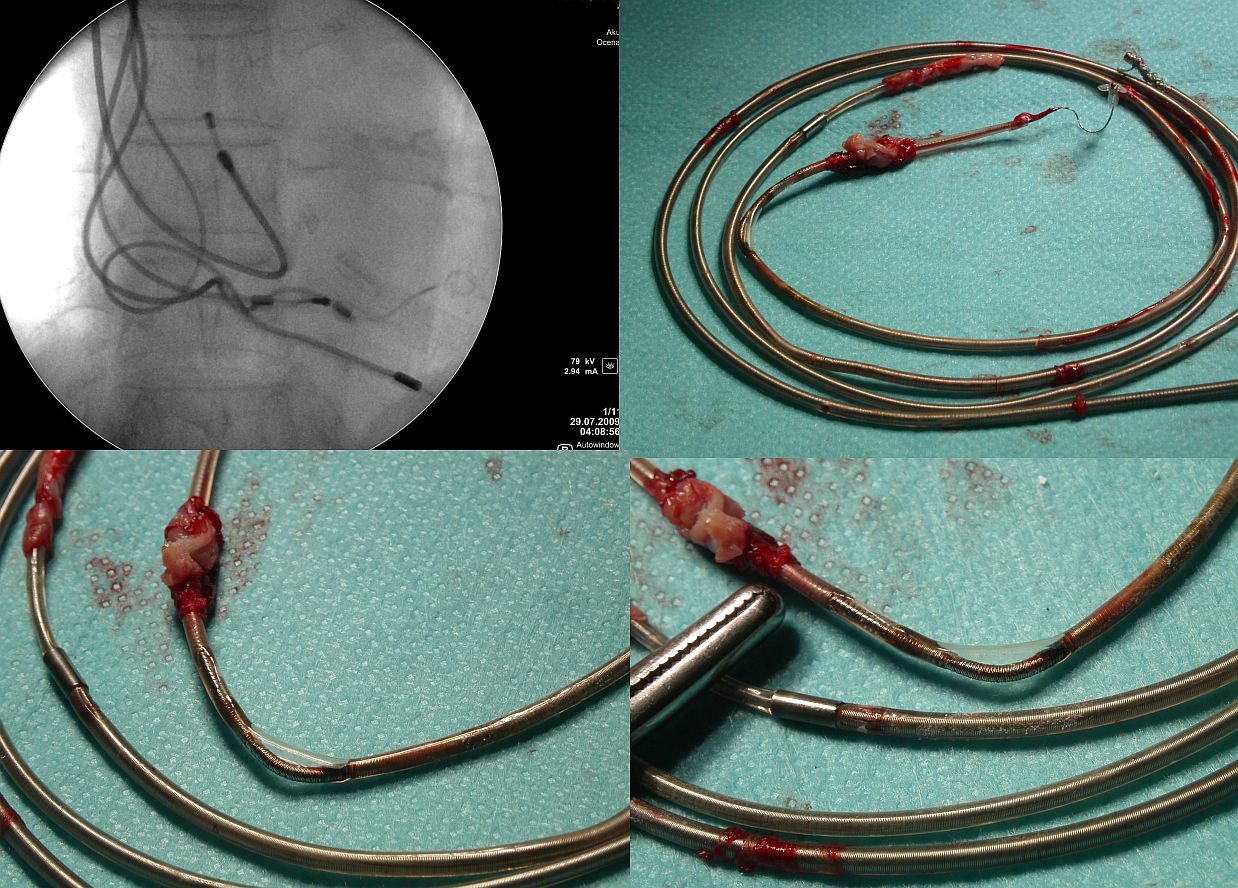

Dopiero jednoczesne całkowite przetarcie dwóch osłonek

elektrod z kontaktem obu spirali (zewnętrznych - gdy

dotyczy elektrod dwubiegunowych) powoduje powstawanie

"trzasków" w obu kanałach powodujących

zjawisko blokowania stymulacji lub wyzwalanie stymulacji w

drugim kanale.

C. W elektrodach defibrylatorowych, w których przebiega

wiele przewodów (dwa do stymulacji/sterowania) dwa do

proksymalnego uzwojenia defibrylującego i ewentualnie dwa

do uzwojenia proksymalnego - objawy zależą od liczby odsłoniętych

przewodów. Najburzliwsze objawy powoduje uszkodzenie

obwodu "pacing/sensing" gdyż

"trzaski" są powodem nieadekwatnych (czasem

licznych) interwencji wysokonapięciowych. Towarzyszą im

różnego stopnia nieprawidłowości z zakresie spadku

amplitudy odbieranego potencjału wewnątrzsercowego, obniżenia

(często wahania) oporności poszczególnych obwodów bądź

wzrostu progu stymulacji.